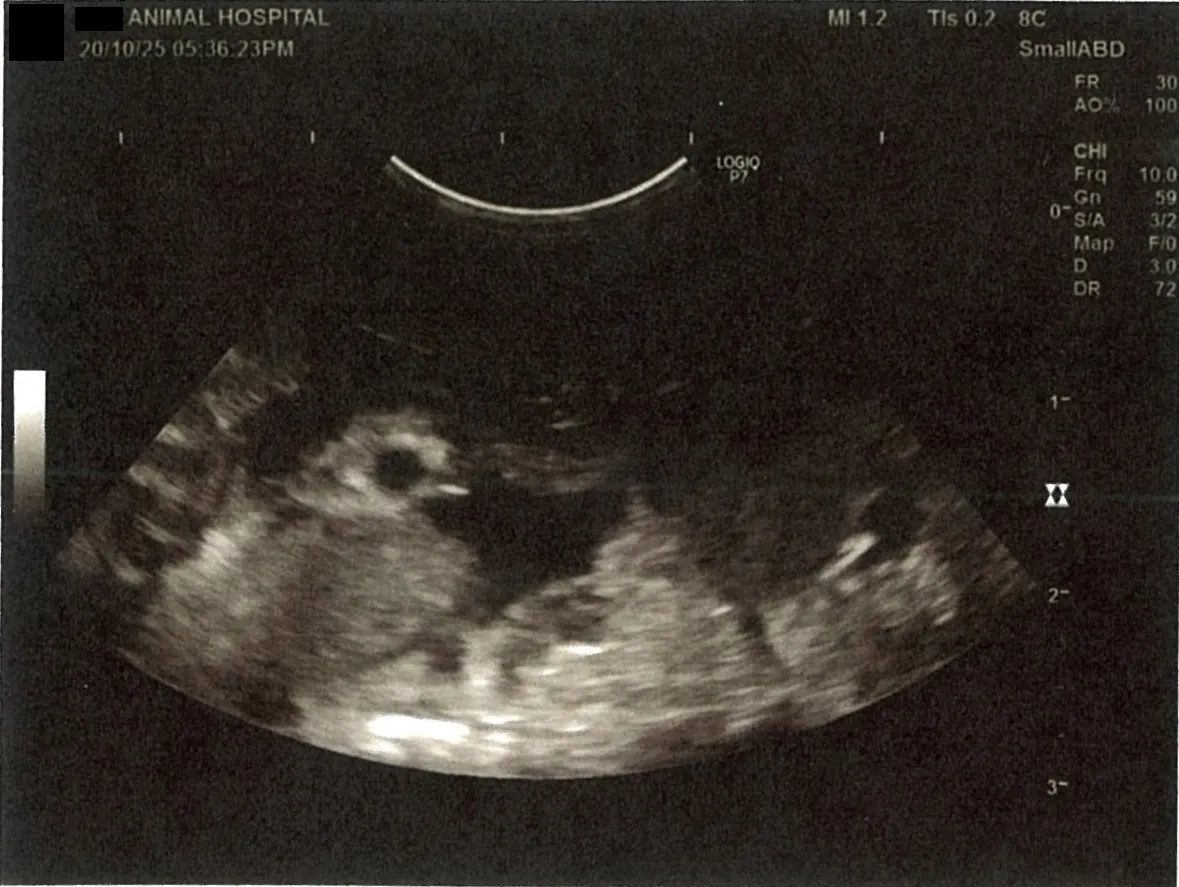

《心臓周りの胸部以外の全ての腹部で腹水がみられるとの診断です》

大網という部分で内臓を包む膜のようなものです。その周りに腹水が溜まっています。

膵臓周りに腹水が確認できるエコー写真

心臓のみ腹水が確認できないエコー写真